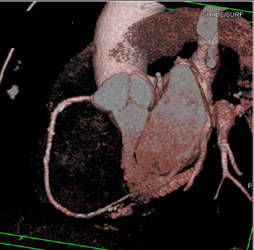

Calcified Bicuspid Valve